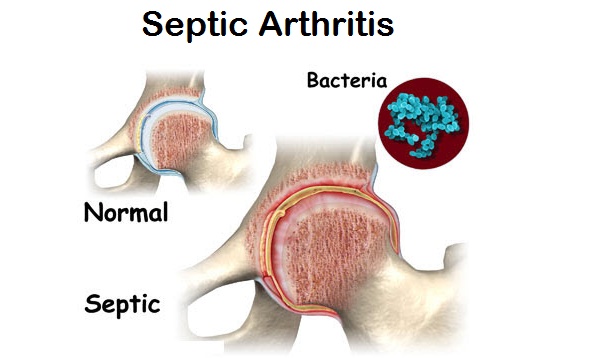

Septic Arthritis:

Septic Arthritis is also known as Infectious Arthritis as it is caused by bacteria or fungus. Septic Arthritis is mostly experienced in one large and single joint in the body; such as, knee or hip. There have been very limited cases of multiple septic arthritis affecting more than one joint in the body. Youngsters and children may develop Septic Arthritis.

Causes:

- An invasion of bacteria within the body

- Bacterial infection post surgery. Knee surgeries are associated with this condition.

- Hemophilias influenza in adults and children leads to septic arthritis

- Hepatitis A, B and C can bring you at advanced risk of developing septic arthritis

- Mumps in children may lead to Septic Arthritis

Symptoms:

- Fatigue and Weakness

- Fever and flu like symptoms

- Redness, tenderness and severe pain around the joint

- Excessive swelling due to fluid accumulation

- Inability to move the body part affected with arthritis